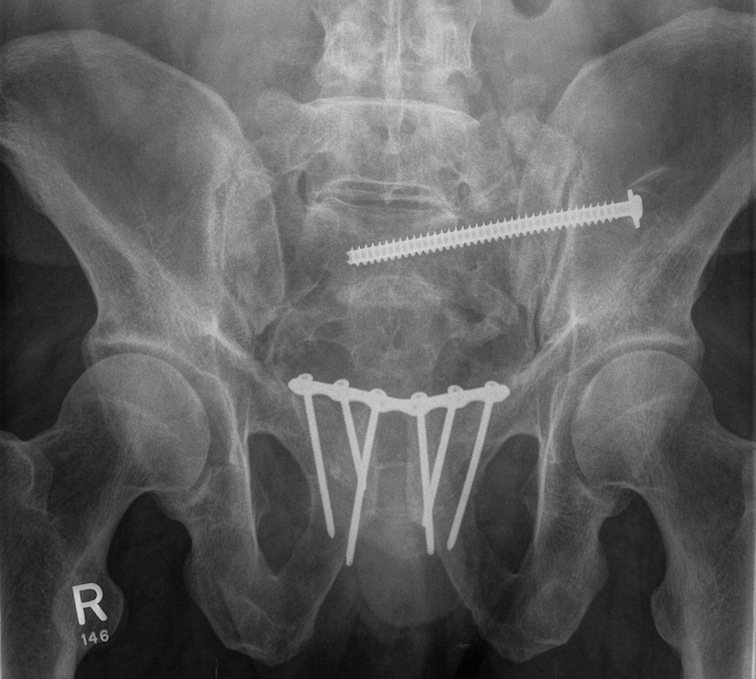

Sacro-iliac screws

Technique

Radiolucent table with image intensifier

- 45o cephalad and caudal / inlet and outlet views

Must reduce SI joint

- reduce vertically with traction on limb / outlet view

- reduce AP usually via anterior plate or external fixation / inlet view

Guide wire insertion into body of S1

- anatomic safe zone

- between S1 foramen and superior ala on outlet view (outlet view)

- between neural canal and anterior body (inlet view)

Insert 6.5 mm partially threaded cannulated screw, to aid compression

Post operative

Check screw position with CT

Protected weight bear for six weeks